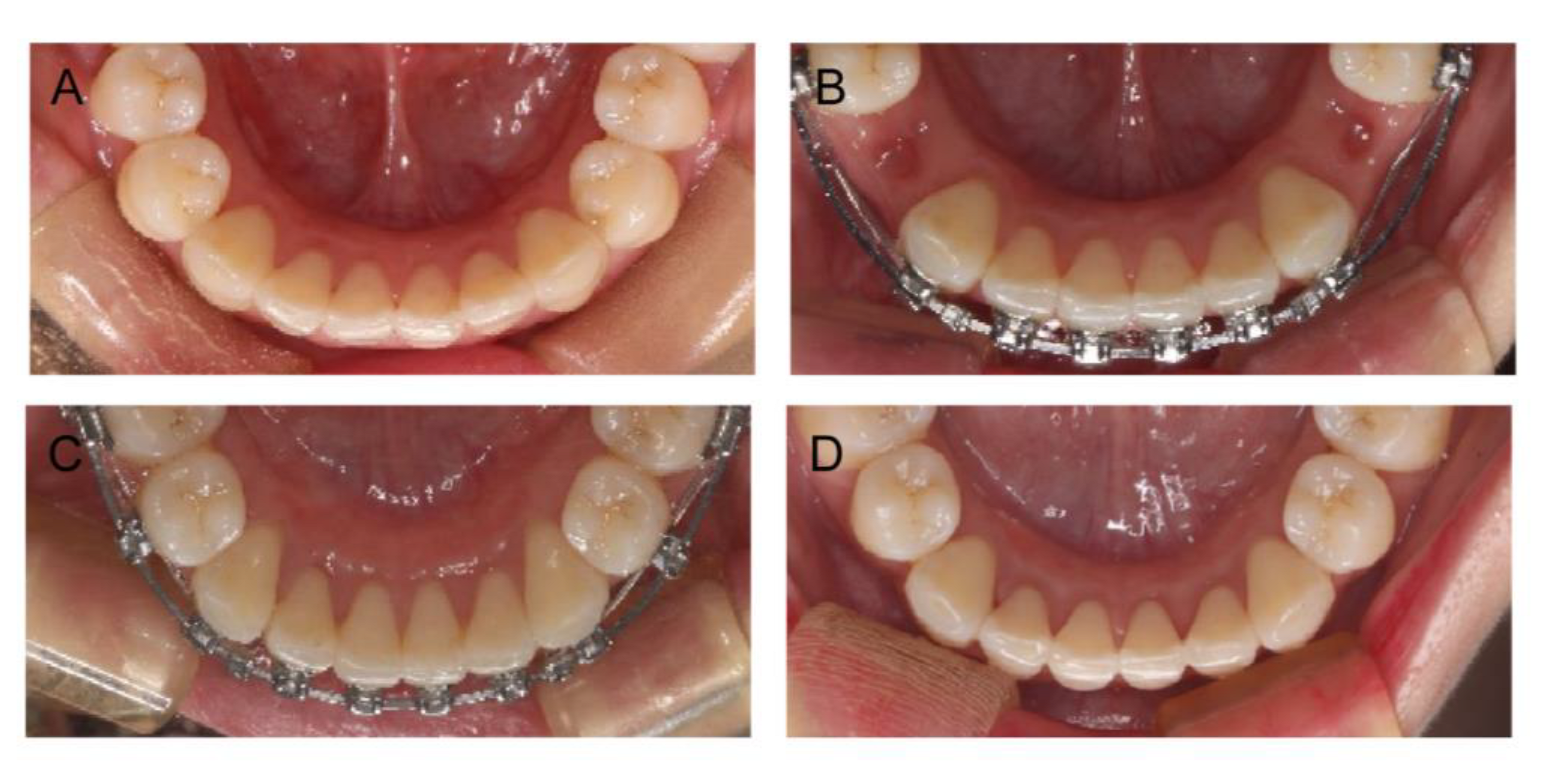

2.4. Treatment Progress

2.5. Treatment Results